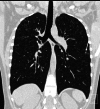

Objectives: Pulmonary Langerhans cell histiocytosis (PLCH) is a rare interstitial granulomatous disease that usually affects young adults who are smokers. Chest computed tomography (CT) allows a confident diagnosis of PLCH only in typical presentation, when nodules, cavitated nodules and cysts coexist and predominate in the upper and middle lungs.

Methods: This article includes a pictorial essay of typical and atypical presentations of PLCH at initial chest CT. Various appearances of PLCH are illustrated and possible differential diagnosis is discussed.

Results: PLCH can present with some aspecific features that may cause diagnosis of the initial disease to be overlooked or other pulmonary diseases to be suspected. In cases of nodule presentation alone, the main differential diagnosis should include lung metastasis, tuberculosis and other infections, sarcoidosis, silicosis and Wegener's disease. In cases of cysts alone, the most common diseases to be differentiated are centrilobular emphysema and lymphangiomyomatosis. Clinical symptoms are usually non-specific, although a history of cigarette smoking, coupled with the presence of typical or suggestive findings at imaging, is key to suspecting the disease. Atypical presentations require surgical biopsy for diagnosis.

Teaching points: • PLCH is a rare interstitial smoking-related disease that usually affects young adults. • The typical first CT shows a mix of nodules, cavitary nodules and cysts in the upper-middle lungs. • Atypical appearance, either cysts or nodules alone, mandates that other diagnoses be considered. • Lung cystic involvement correlates with lung function abnormalities and predicts functional decline. • Integration of the clinical history and imaging results is key to diagnosis.